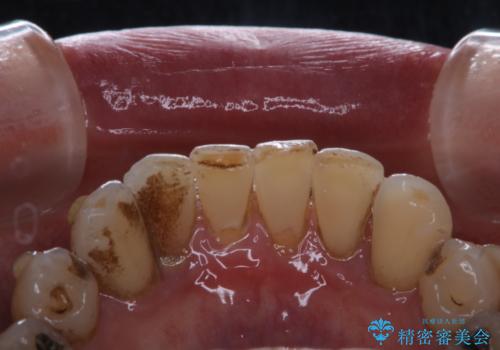

- インビザラインでの矯正中も、コーヒーを頻繁に飲むためステインが気になるとのことでした。PMTC60分コースでなんとかクリーニングを行いました。

インビザライン治療中には、歯の表面にアタッチメント(効率的に歯の移動をするもの)を設定します。そのため歯ブラシでは届きにくい細かい部分などに、歯石や着色がついてしまうことがあります。着色などを放置していると、着色なのか、虫歯なのかの判別もしずらく正確にお口の中の状態を診断できません。